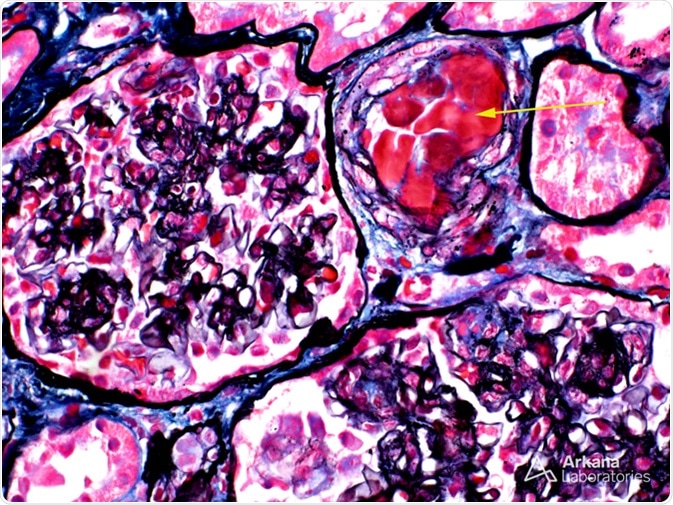

In this image of a combined silver-trichrome stain, the arrow points to the abnormal material within the arteriole lumen. This material was positive for IgM and showed kappa light chain restriction by immunofluorescence, supporting the diagnosis of paraprotein. Interestingly, this kidney biopsy was taken from an 81-year-old man with acute renal failure who had been diagnosed with Waldenström macroglobulinemia (his bone marrow biopsy showed involvement by lymphoplasmacytic lymphoma and he had a circulating IgM-kappa paraprotein). Image Credit: https://www.arkanalabs.com/